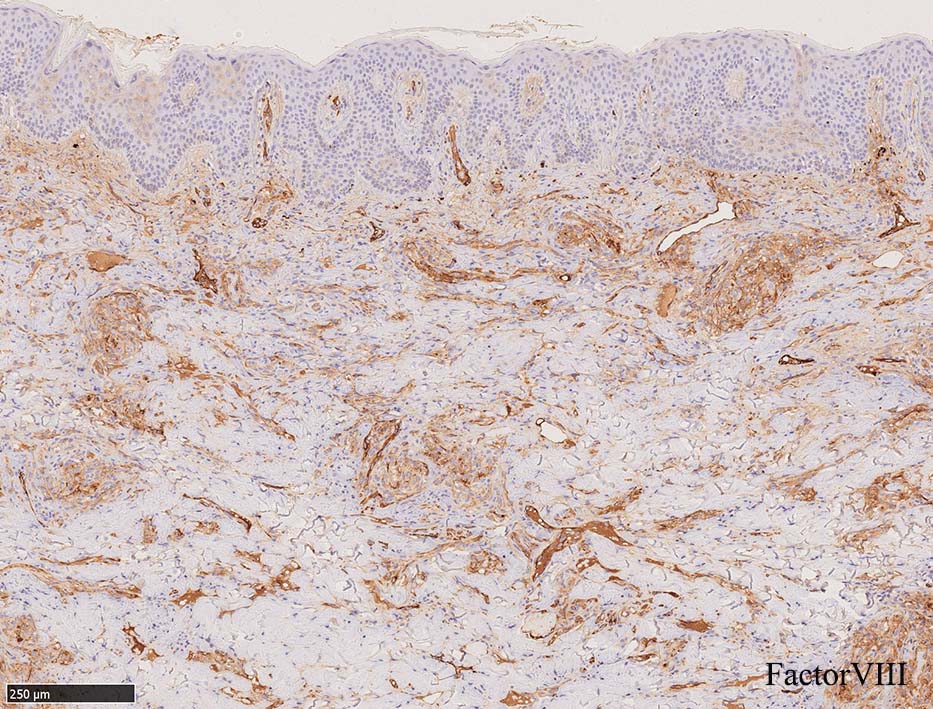

免疫染色, 分子病理学的検査

増生細胞はCD31, CD34, Factor Ⅷ, D2-40などが陽性を示す.

HHV-8の潜伏期関連抗原(HHV-8 Latency-associated nuclear antigen: HHV-8 LANA)が市販されており, 核が点状に染色される陽性所見がKaposi肉腫の確定診断に必須となっている.